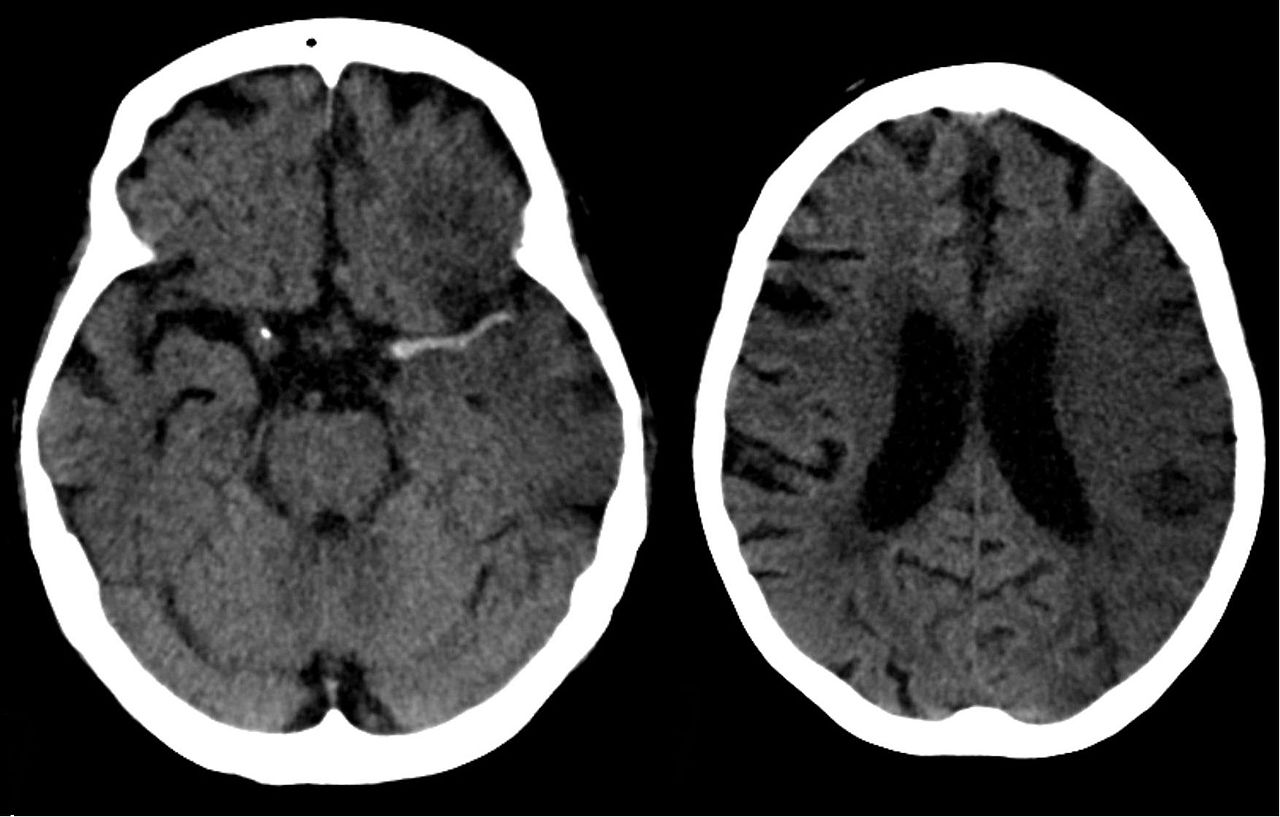

The significance of the brain in the human body need not be reconsidered. In any case, the elements influencing brain health should be seen better. On the off chance that the brain isn’t dealt with appropriately, it could lead to problems like stroke. Here are some ways you can prevent a stroke: